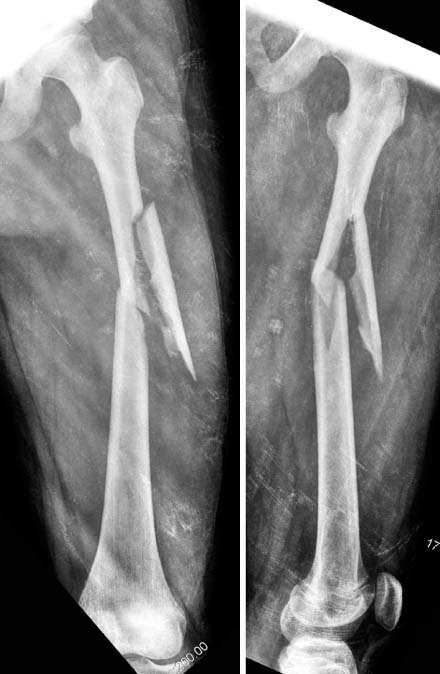

Fig. 3

Although the femoral fracture was well reduced by flexible nails (left), the nails were bent and varus deformity occurred because the patient had a weight-bearing too early (right).

Fig. 3 Although the femoral fracture was well reduced by flexible nails (left), the nails were bent and varus deformity occurred because the patient had a weight-bearing too early (right).